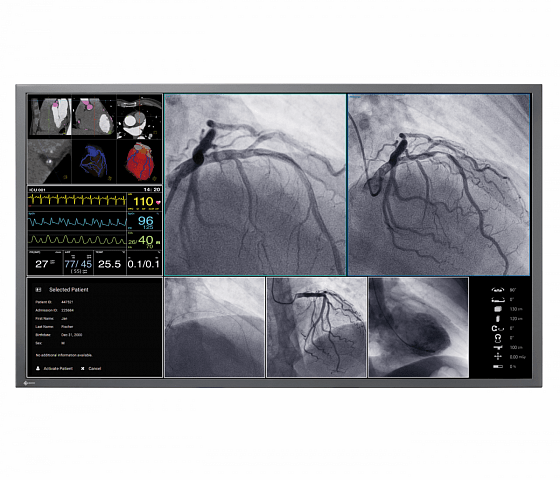

Der 55" Breitbild-Monitor mit 4K UHD Auflösung ist ideal für die Anzeige medizinischer Bilder in der Angiographie, Kardiologie oder Endoskopie geeignet und kann sowohl an der Wand als auch an eine Deckenhalterung montiert werden. Das Sicherheitskonzept und die langlebige Hintergrundbeleuchtung sind ideal für einen langfristigen, stabilen und verlässlichen Einsatz.

- Optimale Anzeige von DICOM Bildern durch Graustufenabgleich nach DICOM Part 14 Standard ab Werk.